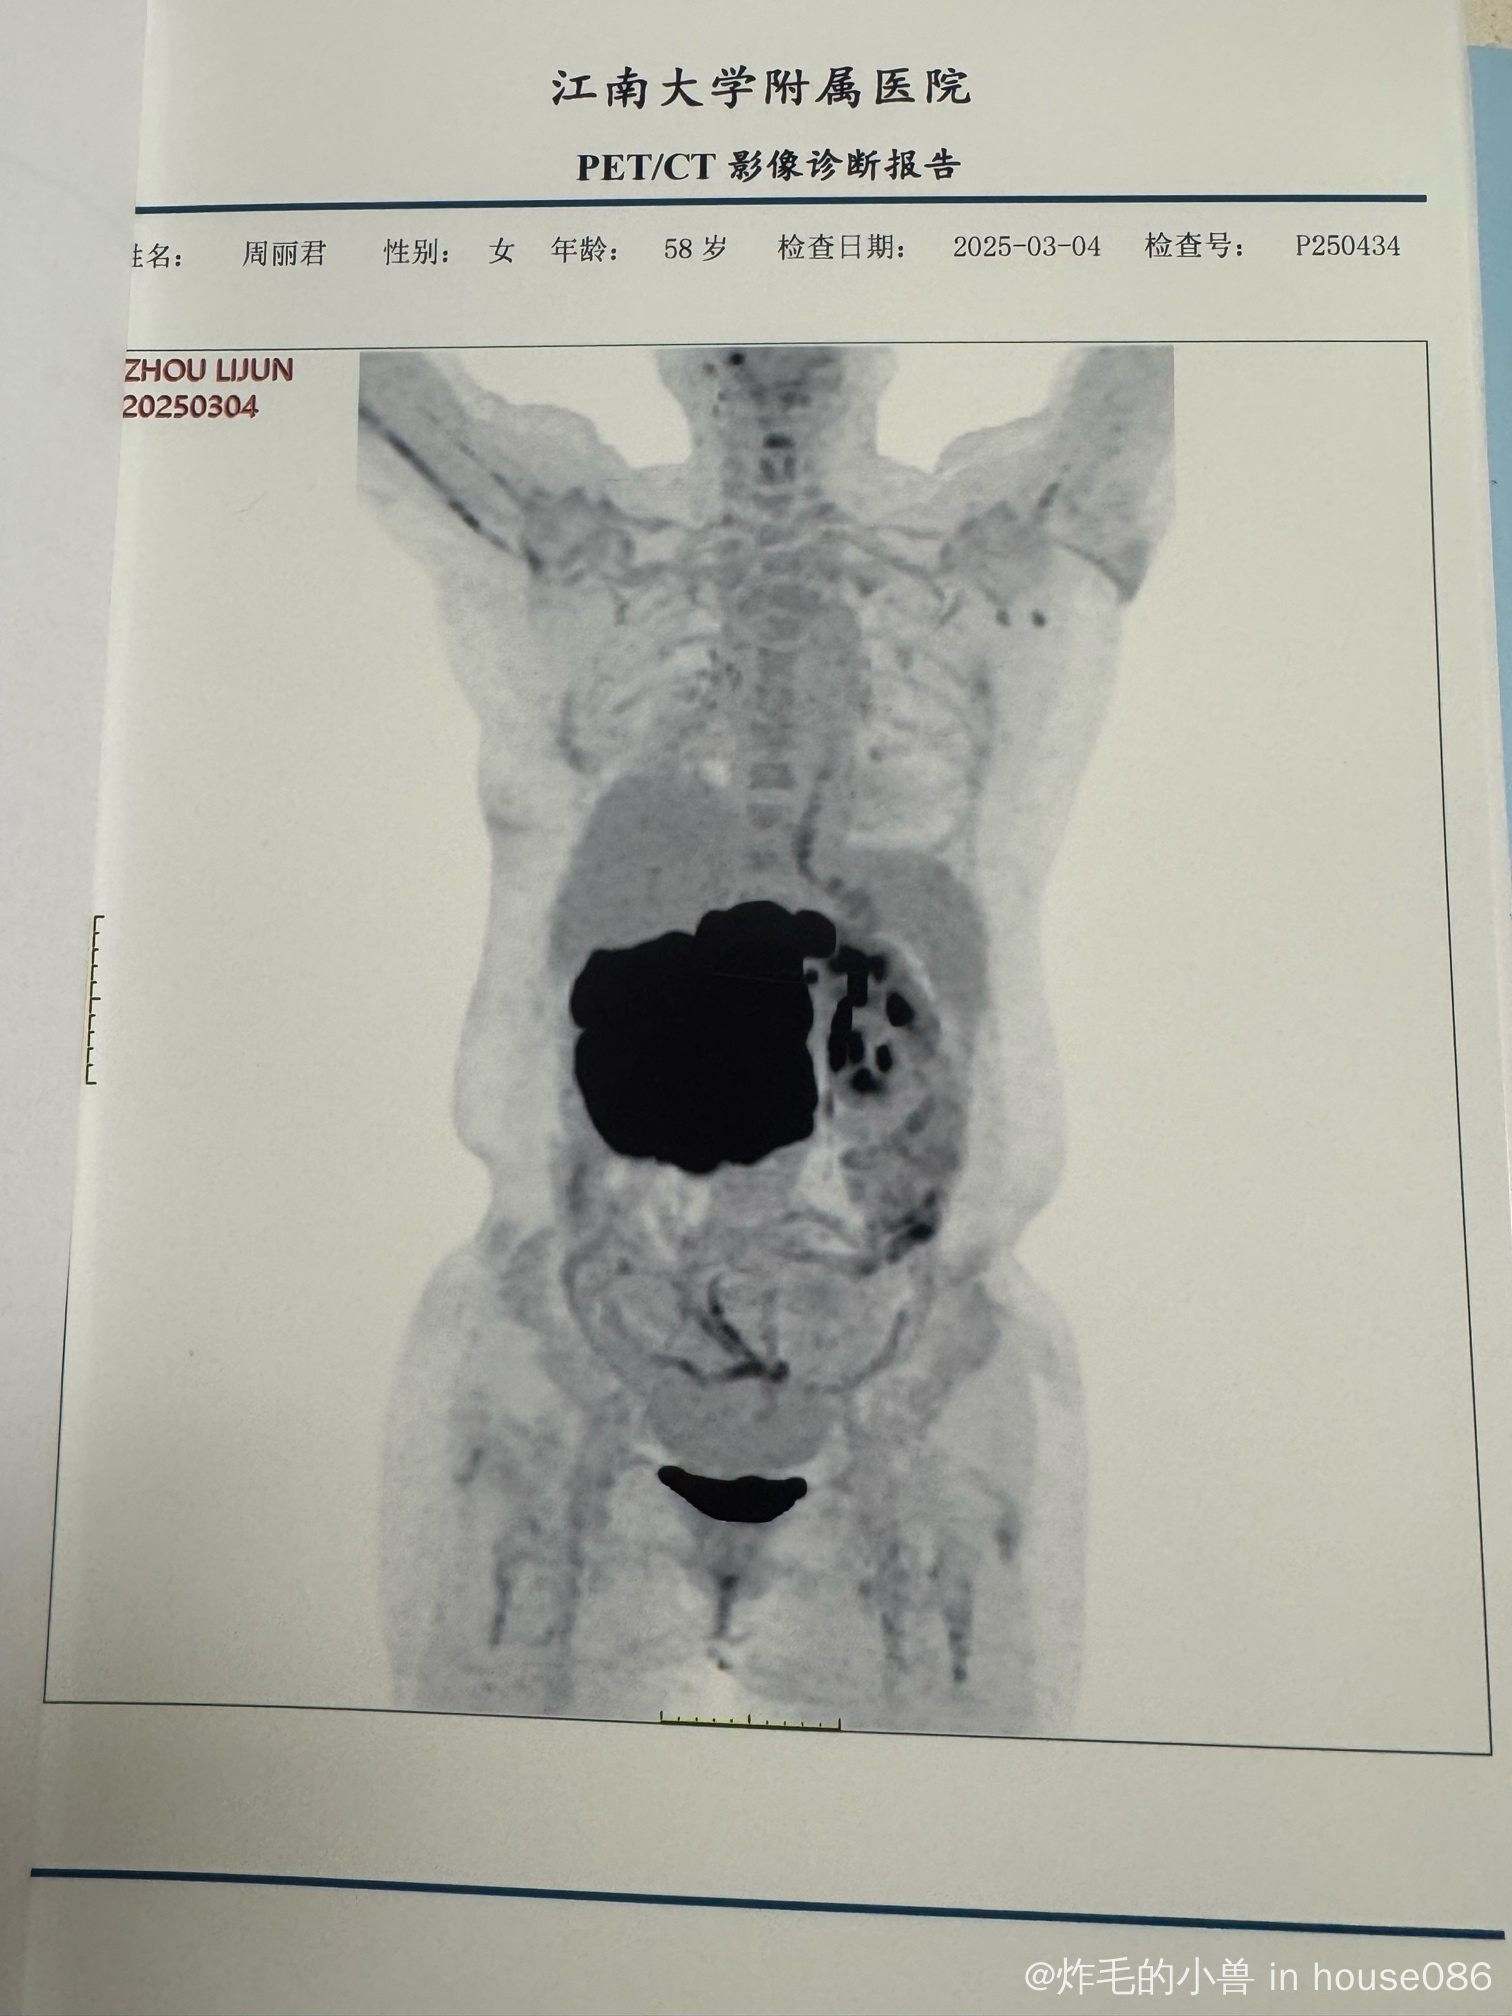

有没有类似的淋巴瘤患者,我妈年后查出来的,现在全家都心情沉重

系统性间变大细胞

带着片子去咨询过上海2家医院了,我们家在无锡,建议我们就在江大附属医院医治的,苏州也请了权威来无锡会诊过了,方案没啥区别